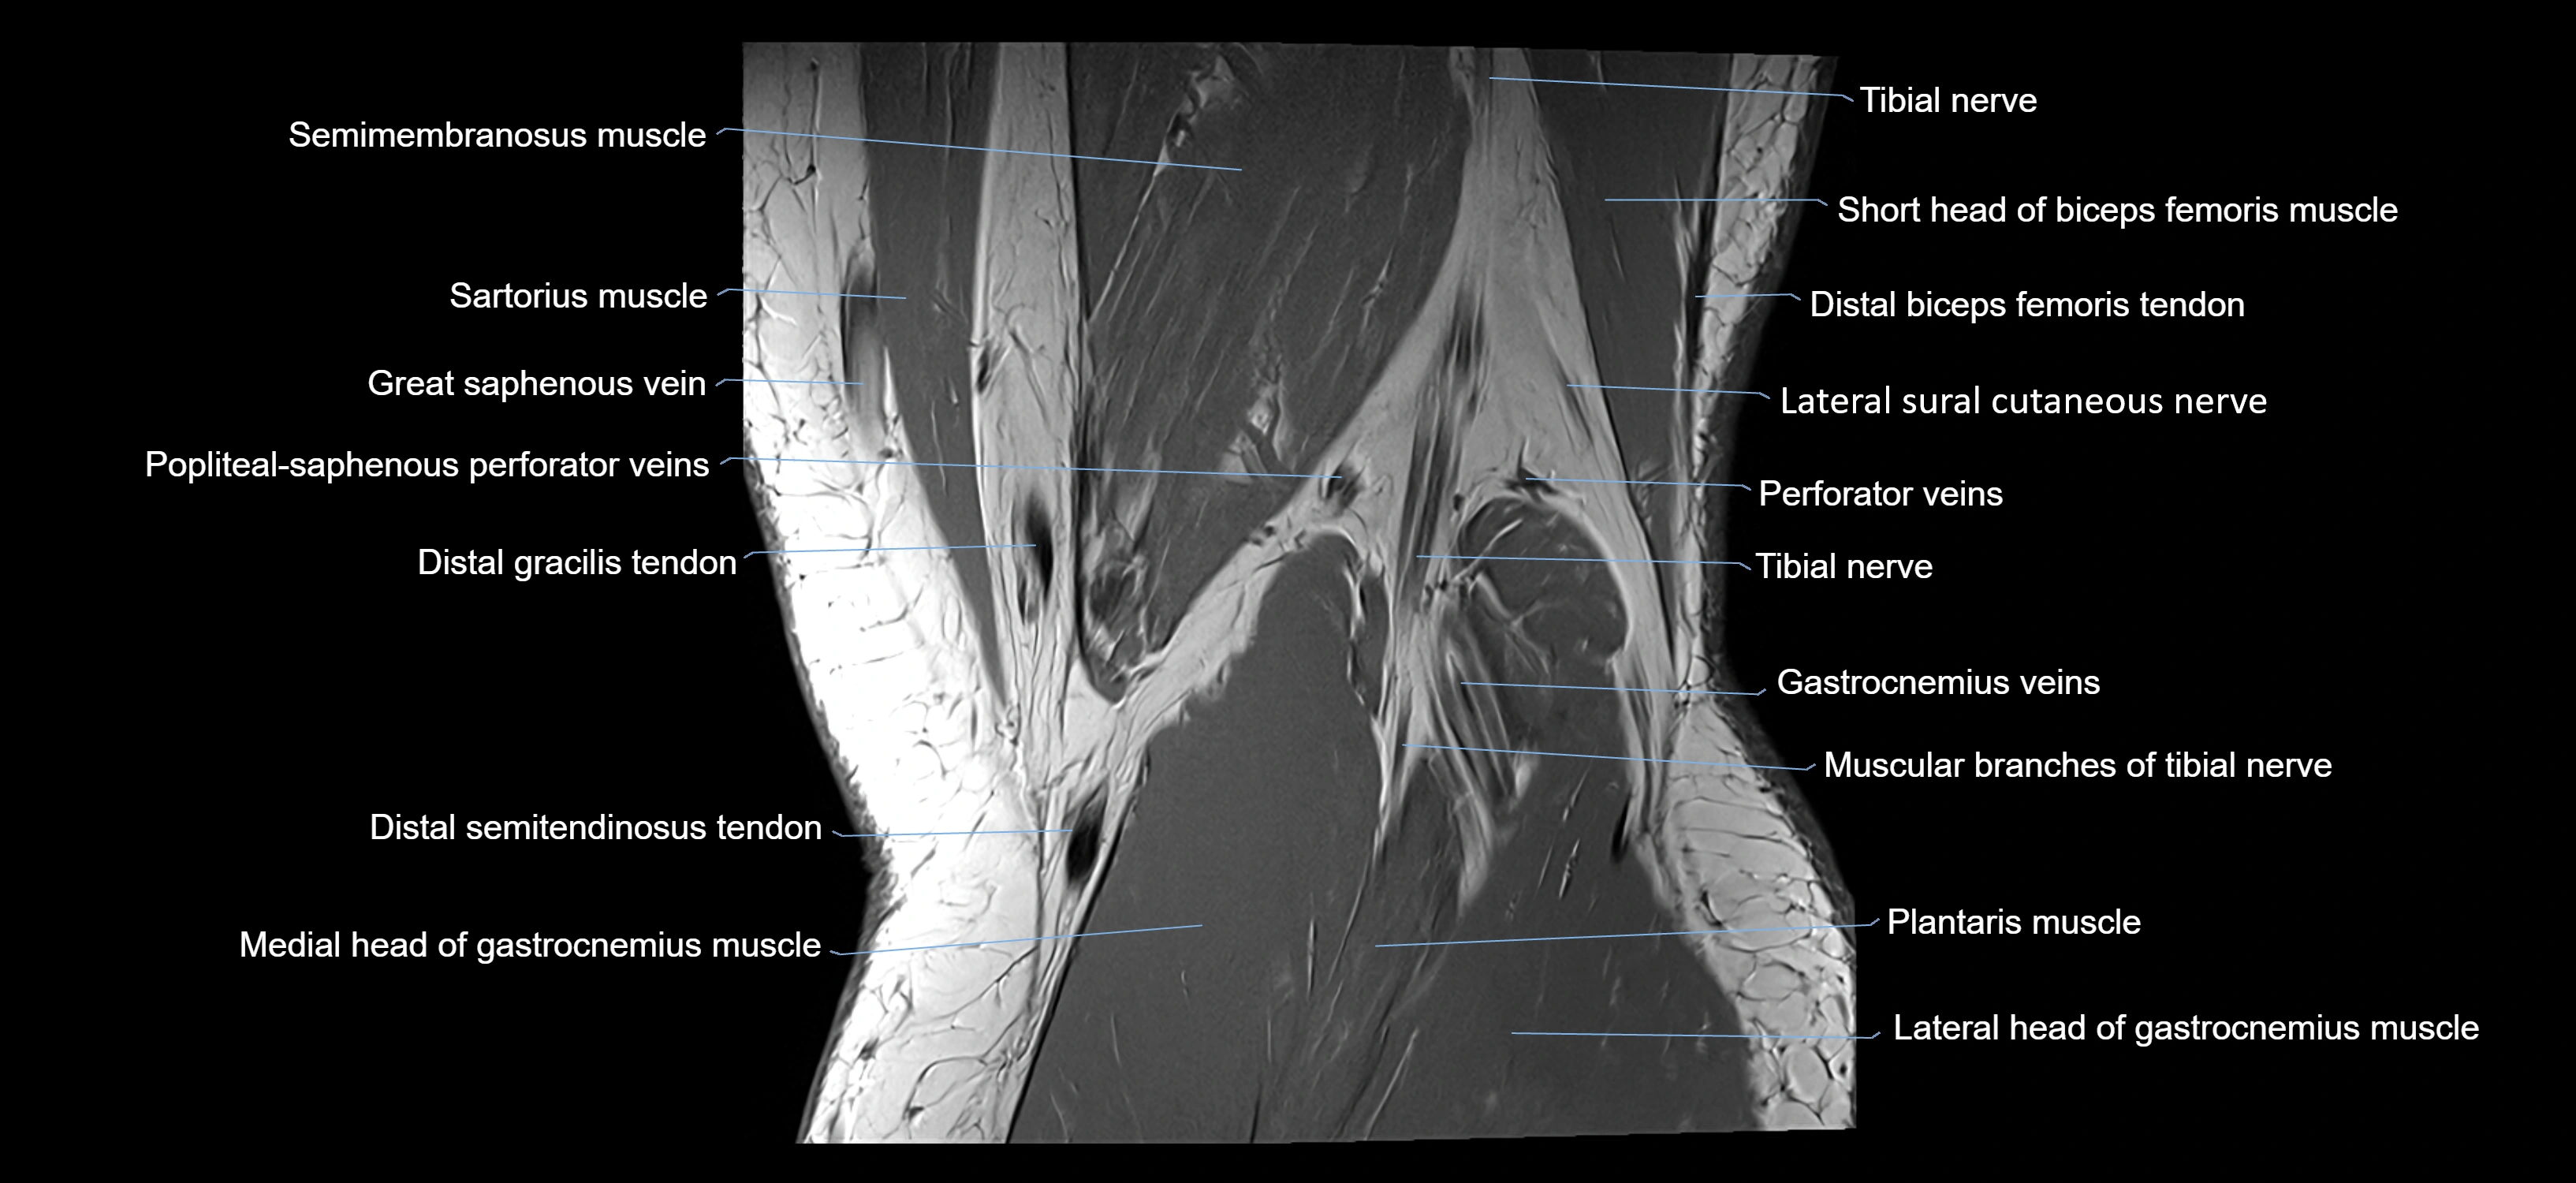

- Gracilis tendon (Distal)

- Medial gastrocnemius tendon

- Medial head of gastrocnemius muscle

- Plantaris muscle

- Popliteal vein

- Popliteal–Saphenous perforating veins

- Sartorius muscle

- Semimembranosus muscle

- Small saphenous vein

- Tibial nerve

- Lateral sural cutaneous nerve

- Medial sural cutaneous nerve

- Muscular branches of tibial nerve